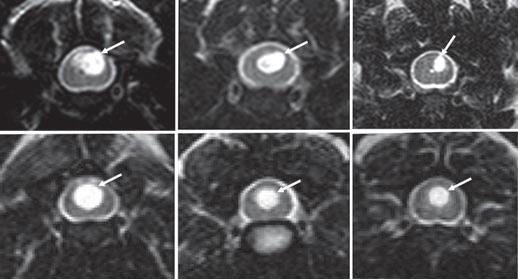

In an

October 2021 article, Drs. Srdjan Cirovic and Clare Rusbridge report

on a computer model they devised

which may explain how SM syrinxes (syringes) are created and expand, due to the impulsive movement of

cerebrospinal fluid (CSF), called "slosh". A magnetic resonance imaging

(MRI) scan of a cavalier was used as the model

design for the study. The investigators conducted simulations of various

spinal cord conditions, from the cord being free of cavities to small

syringes at different locations to a prorgessively expanding syrinx.

(See Figure 2.)

They found that, if small syringes are present, there are peaks of

stress at those locations, the effect being most pronounced at the

locations at which syringes initially form. When the syrinx reaches the

lumbar region, the stress becomes moderate. They concluded that their

findings support the "slosh" hypothesis, suggesting that small cervical

syringes may progress, but when the syrinx is large, there is less

stress, which may explain why a syrinx can rapidly expand but then

remain unchanged in shape over years. Their stated conclusions:

"The results of this study strongly suggest that the spinal cord tissue in the vicinity of fluid-filled cavities experiences higher than normal mechanical stress due to the movement of the CSF from epidural excitation. When the syringes are longer than approximately 30 mm, filling of the epidural veins may generate the "slosh" effect, where the fluid is forced to the caudal end of the syrinx. The results for the simulations of an expanding syrinx are broadly consistent with the homeostatic hypothesis, as the stress in the cord is lower for the fully developed syrinx than for smaller syringes. Other, potentially more realistic, scenarios for syrinx expansion should be examined in the future. This study specifically addresses syringomyelia in dogs, and more specifically in CKCS. ... Considering anatomical and other differences (e.g., upright posture in humans) the results regarding the potential pattern of syrinx enlargement do not apply to humans or to dog breeds other than CKCS."